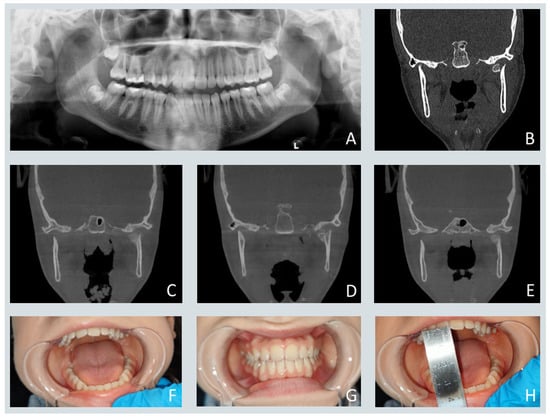

Pediatric Maxillofacial Fractures: Patterns of Injury, Surgical Indications, and Treatment Outcomes: A Five-Year Retrospective Study

Background: Pediatric craniofacial fractures represent a distinct clinical entity characterized by unique anatomical and developmental factors that differentiate them from adult facial trauma. Despite their relative rarity, these injuries pose diagnostic and therapeutic challenges due to the presence of active growth centers and [...] Read more.

Background: Pediatric craniofacial fractures represent a distinct clinical entity characterized by unique anatomical and developmental factors that differentiate them from adult facial trauma. Despite their relative rarity, these injuries pose diagnostic and therapeutic challenges due to the presence of active growth centers and the potential for long-term functional and esthetic sequelae. Methods: A retrospective observational study was conducted among pediatric patients aged 0–17 years treated for craniofacial fractures between 2020 and 2024 at the Department of Cranio-Maxillofacial Surgery, University Hospital in Kraków, Poland. Demographic data, injury mechanisms, fracture distribution, treatment modality, and associated injuries were analyzed. Multivariate logistic regression was applied to identify predictors of surgical intervention. Results: Ninety-eight patients met the inclusion criteria. The mean age was 12 years, with a male predominance. Midfacial fractures were most common, with orbital floor fractures representing the single most frequent injury. Surgical management was performed in 72 cases, predominantly using the transconjunctival approach and autologous bone grafting. Orbital floor fractures were identified as the only independent predictor of operative treatment (p < 0.05). Central nervous system trauma was the most frequent concomitant injury. No significant changes in etiology or fracture distribution were observed during the COVID-19 pandemic. Conclusions: Pediatric craniofacial trauma follows a reproducible, age- and mechanism-dependent pattern. Effective management requires individualized, growth-preserving, and function-oriented treatment strategies. Standardization of care protocols and multicenter prospective studies are essential to optimize outcomes and develop evidence-based, age-specific guidelines for the management and prevention of pediatric facial fractures. Full article